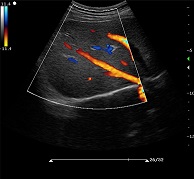

? ? ? ?C7為深圳安盛生物醫(yī)療技術(shù)有限公司新一代便攜式彩超產(chǎn)品,采用了先進(jìn)的PC平臺(tái),擁有強(qiáng)大的處理能力,優(yōu)異的圖像性能,集小巧輕便、全面的功能與輕巧流暢、特有的U型設(shè)計(jì)與一身,提供大眾新選擇。

支持凸陣、線陣、腔內(nèi)、相控陣、小微凸等探頭

? ?● 多種成像模式

? ? ? ?B、C、PW、CW、BCD三功、大角度偏轉(zhuǎn)成像、實(shí)時(shí)寬景成像、梯形成像(僅支持線陣)、解剖M型、彩色M型成像、組織多普勒成像、3D/4D成像

? ?● 彩色多普勒增強(qiáng)技術(shù)

? ? ? ?有效抑制彩色血流閃動(dòng)噪聲,提高血流分辨率和靈敏度